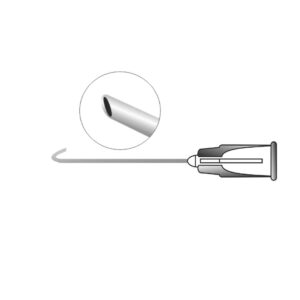

Description

A precision ophthalmic cannula designed for controlled fluid injection during cataract surgery to separate the lens nucleus from the capsule. It facilitates smooth nucleus rotation and safe cortical removal by creating a balanced fluid wave. Manufactured with a fine, atraumatic tip to ensure accurate hydro dissection and enhanced surgical control.

Available in disposable and Reusable